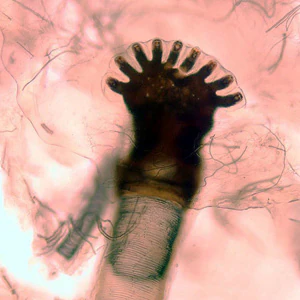

A 25-year-old man, who recently returned from a trip to Brazil, presented to his health care provider with a festering lesion on his forehead. The patient also complained of feeling things moving under his skin. Surgical removal of the outer surface of the lesion revealed several maggot-like organisms (Figure A) beneath the skin. Specimens were sent to the CDC for diagnostic assistance. Figure B shows a close-up of the anterior end of one of the organisms; Figure C shows a close-up of the posterior end. Figures D and E show structures dissected out of the anterior end of one of the organisms. What is your diagnosis? Based on what criteria?

Figure A